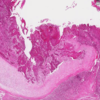

Bronchial squamous dysplasia

Squamous metaplasia

Sqamous dysplasia

Carcinoma in situ